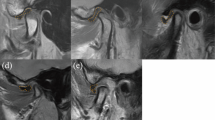

At the end of conservative follow up, MRI showed condylar bone intact in 6 patients with 8 joints (23.5%), condylar surface bone destruction (Wilks IV, V stages) in 13 patients with 14 joints (41.2%, Fig. 2), and severe bone resorption in 7 patients with 12 joints (35.3%, Fig. 3, Table 1).

Disc displacement and condylar bone destruction in the end stage.

(A) Decreased joint space post injury by coronal CT reconstruction (arrow). (B) Condylar bone resorption 3 months post injury by coronal CT reconstruction. (C) MRI showed right disc displacement with condylar bone destruction (arrow). (D) MRI showed left disc displacement with condylar bone destruction (arrow).